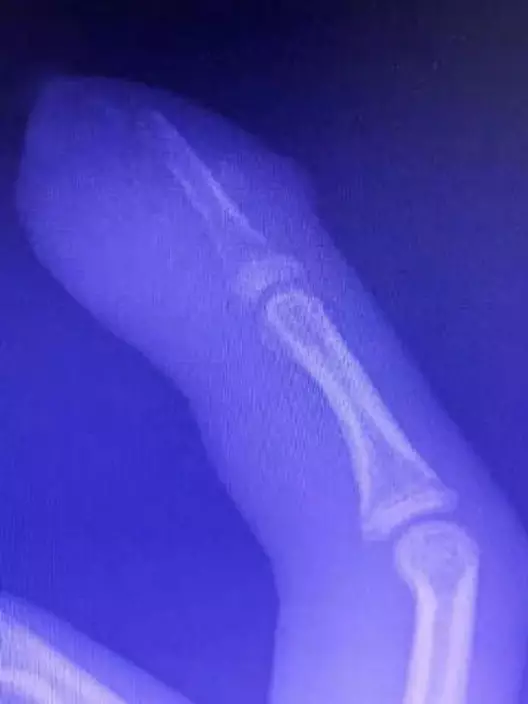

X光片發現少年指骨也出現嚴重感染。網圖

由外科副主任醫師李濤看了X光片後發現,少年的手只不僅皮膚化膿,指骨也出現嚴重感染,必須立刻進行手術,否則可能要截肢,最後清除了所有壞死的骨組織,順利保住了手指。